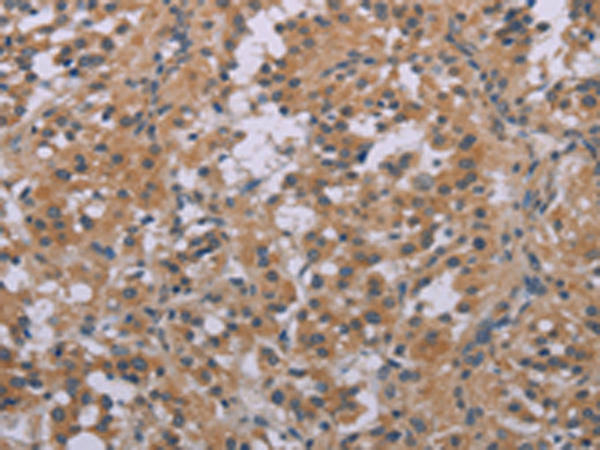

IHC positive control: |

Human thyroid cancer and Human brain |

IHC Recommend dilution: |

25-100 |